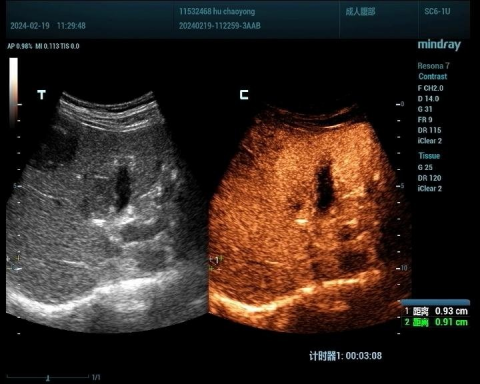

肝癌病例1